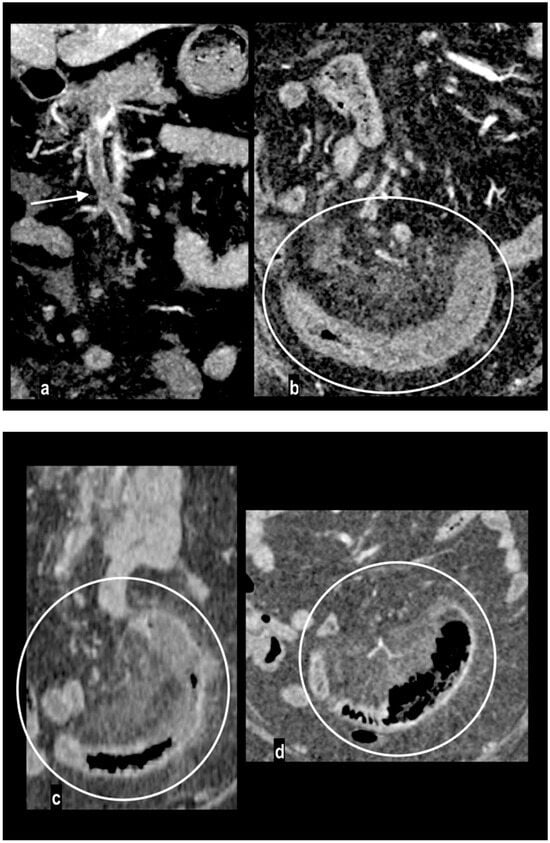

Figure 7.

Abdominal pain in a 67-year-old female with a recent SARS-CoV-2 infection. Porto-mesentic partial thrombosis at coronal portal MPR ((a) arrow). Segmentary ischemic injury of an ileal loop with parietal hypoenhancing thickening and mild mesenteric haziness ((b) circle). The patient was treated with anticoagulant therapy. MDCT performed 4 and 7 days later ((c,d) circles) showed progressive parietal thinning with disappearance of intestinal wall line on mesenteric side, suggesting transmural necrosis. The patient underwent surgical resection of the necrotic loop.

Venous mesenteric thrombi are visualized as filling defects within the venous lumen. The vessel wall can appear as an enhancing rim. The venous outflow is interrupted, determining the engorgement of mesenteric veins [29]. Mortality in veno-occlusive mesenteric ischemia reaches 44% but is lower than in patients with arterial ischemia. Because intestinal necrosis occurs later due to the underlying pathomechanism, the first therapeutical approach is with anti-coagulation therapy that may improve the clinical picture in 24–48 h. When bowel necrosis occurs, only the damaged bowel loops are resected (Figure 7) [9,58,64].

Mesenteric ischemia by venous occlusion is determined by porto-mesenteric vein thrombosis. It is the least common cause of mesenteric ischemia (5–20% of cases) and occurs in younger patients. Hypercoagulability syndromes (antiphospholipid antibody syndrome, protein C and S deficiency, etc.) or states (pregnancy or oral contraceptives); a decreased porto-mesenteric blood flow, particularly in chronic liver disease; and a porto-mesenteric involvement in neoplastic, necrotizing pancreatitis, inflammatory or traumatic concurrent pathologies are the more common risk factors [62]. Porto-mesenteric thrombosis may also occur for extrinsic compression from tumor encasement [60]. Primary mesenteric venous thrombosis without an underlying disease has also been described [63]. The clinical onset of venous thrombosis is subacute because ischemia develops gradually and more slowly than arterial ischemia. Venous bowel infarct requires the extensive involvement of the upstream peripheral arcade of the vasa recta branches. For these reasons, patients complain of subacute long-standing symptoms for about 2–4 weeks and may present nausea and vomiting [6].